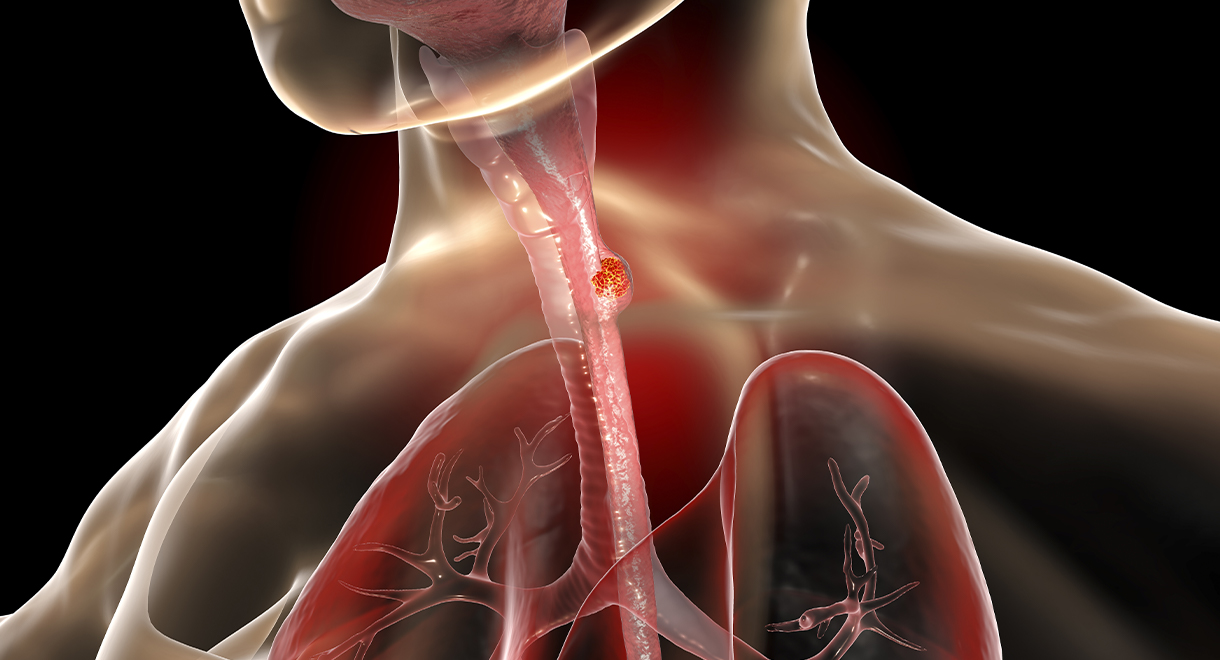

Dramatic Rise In Esophageal Cancer

The incidence of esophageal cancer has risen dramatically in recent years. According to World Health Organization cancer data, esophageal cancer...